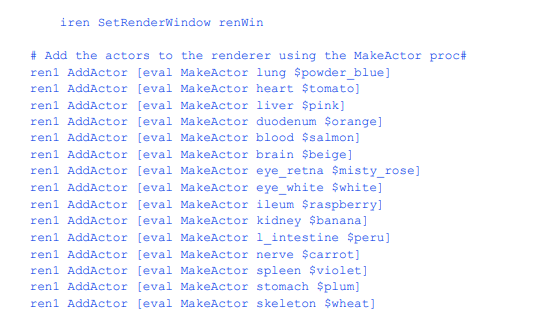

一旦模型按照上述流程生成,就可以使用下面的名为ViewFrog的tcl脚本进行渲染。tcl。首先,我们创建一个Tcl过程来自动从模型文件中创建角色。所有管道元素的命名都与部件的名称后面跟着管道元素的名称一致。这使得用户很容易在更复杂的用户界面中识别每个对象。

在创建所需渲染对象的常规代码之后,为每个部分创建一个可以添加到渲染器的actor:

脚本的其余部分定义了一个标准视图。

图12 - 9显示了用ViewFrog生成的青蛙的四个视图。tcl。这个冗长的示例展示了像VTK这样的综合可视化系统的强大功能。